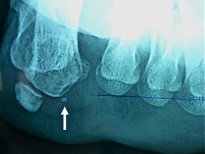

absence de sésamoïde interne sur un pied jamais opéré |

Leur fragmentation est en revanche assez fréquente (10 à 30 % de la poplulation).

Elle atteint plus souvent le sésamoïde interne.

Le sésamoïde est appellé bipartita s'il est en deux fragments, multipartita s'ils sont plus nombreux.

La fragmentation est non douloureuse dans les conditions normales.

Exemple de sésamoïde interne fragmenté sans douleur: